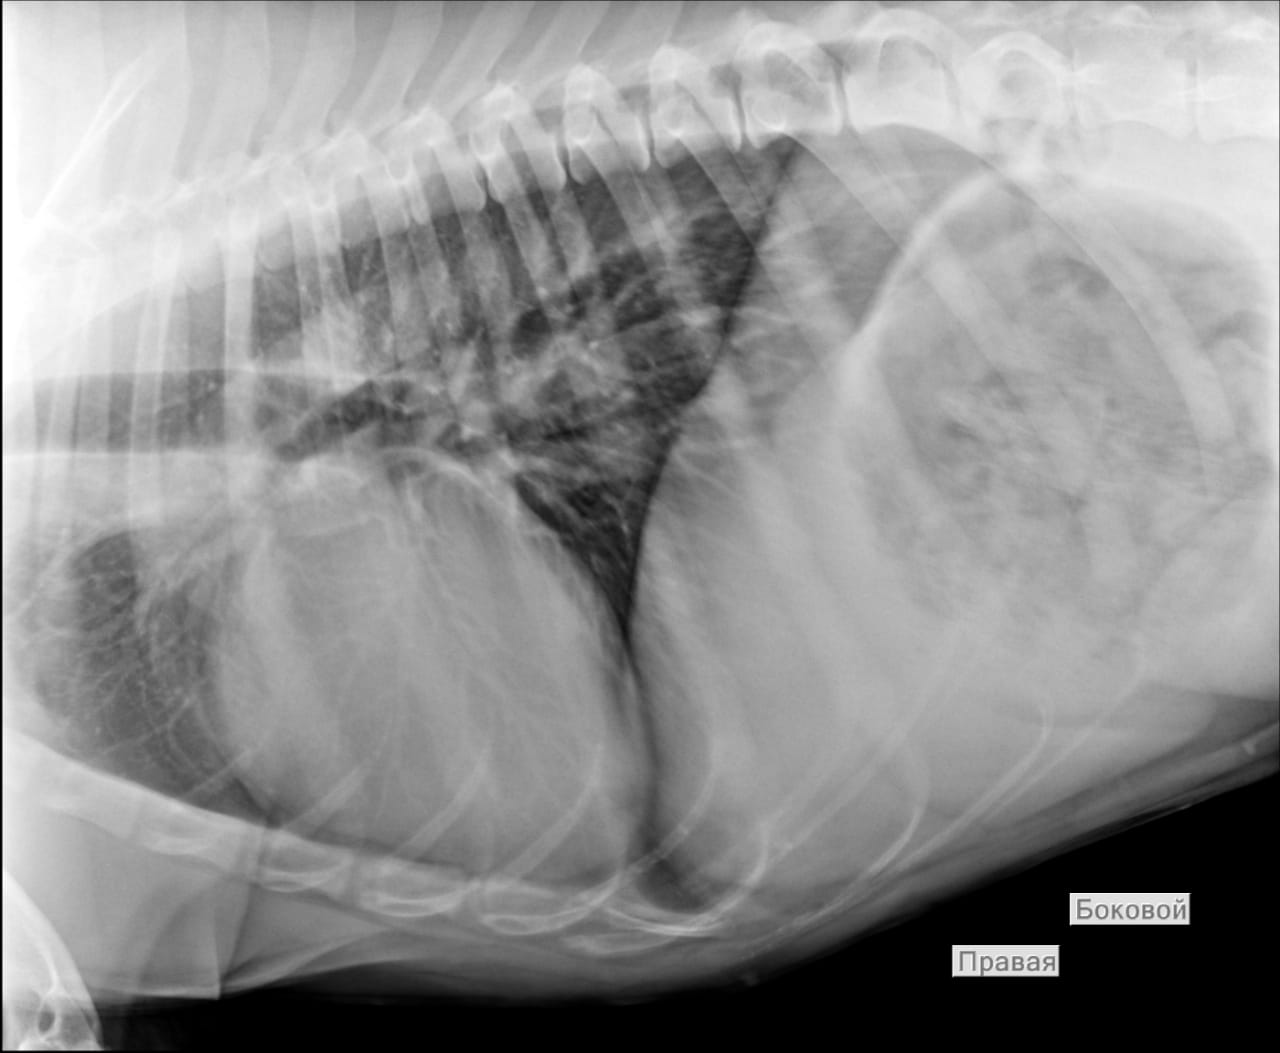

Анализы Арчи. Сердца и легких

Вложения

IMG-20220719-WA0100.jpg

IMG-20220719-WA0102.jpg

IMG-20220719-WA0104.jpg

IMG-20220719-WA0103.jpg

IMG-20220719-WA0105.jpg

Сегодня Арчуна Ирина возила на рентген легких и сдали анализ мочи. Результат анализа мочи готов будет завтра. Рентген легких выставляю.

Ирина, ждем твоего вердикта по рентгена и можно ли нам готовить Арчи к операции по глазам.

Антибиотика курс пропили.

Лучше чем было, но явно не норма:(